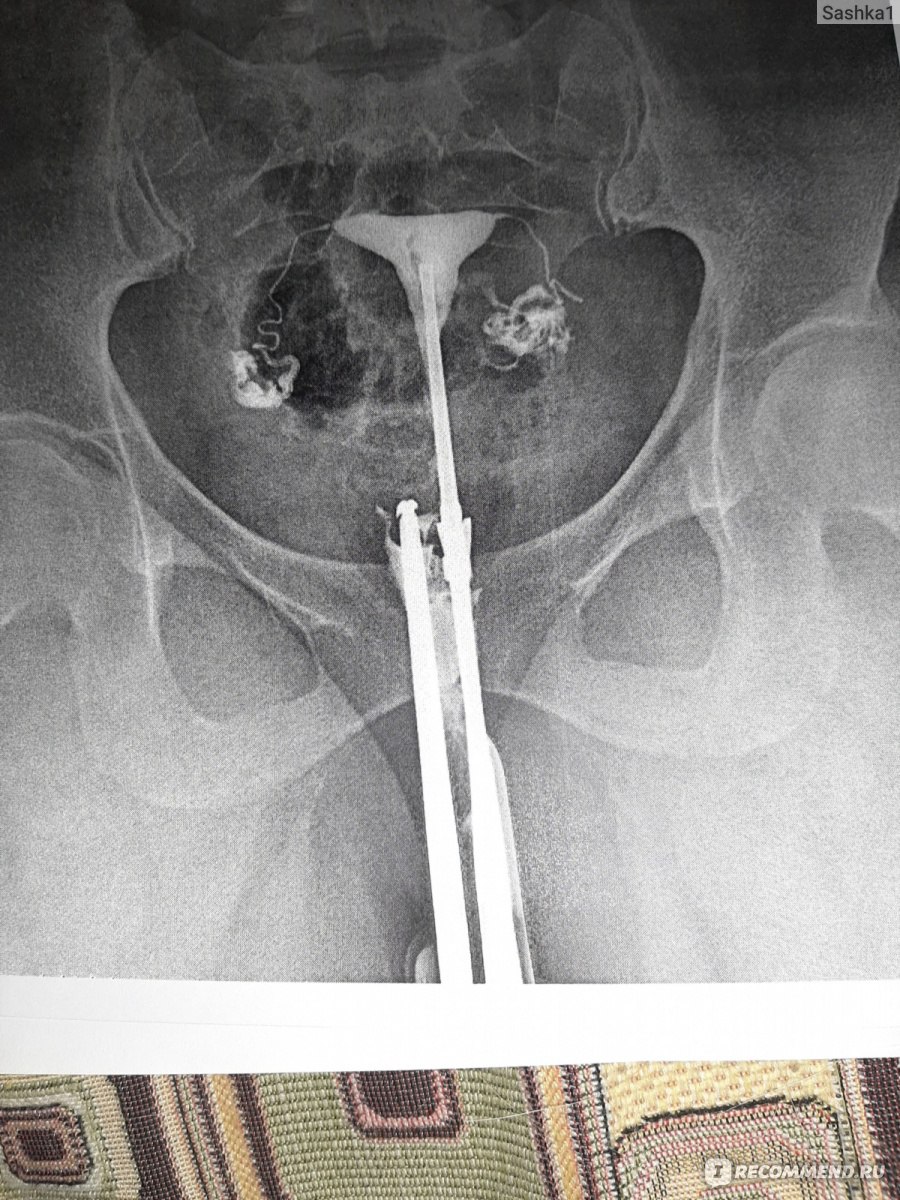

Гистеросальпингография: описание и фотографии